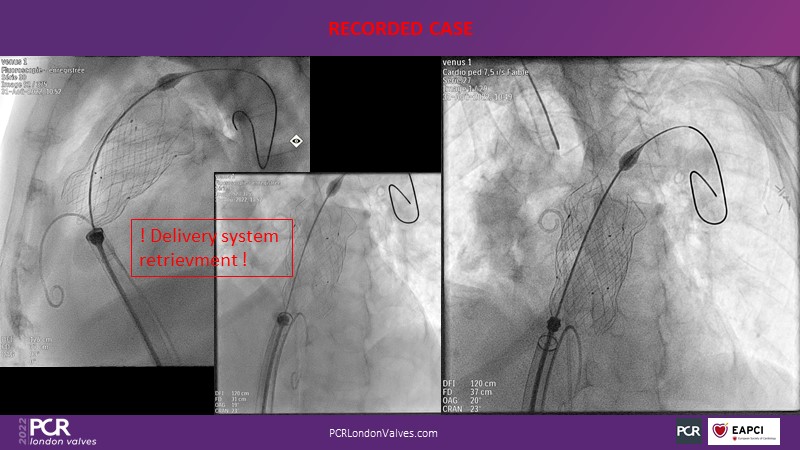

In this session from PCR London Valves 2022, discover the new Venus MedTech technology for tricuspid and pulmonary valve replacement, and a review of the clinical indications, selection criteria and procedural details.

- To learn about Venus MedTech technology, clinical indications and procedural details of valve replacement systems

- To learn more about the clinical experience and outcomes with Cardiovalve tricuspid and Venus P-valve